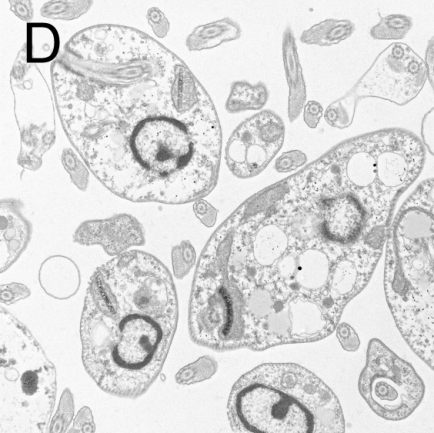

图2 利什曼原虫形态结构

A:前鞭毛体染色显微照片[4],B:前鞭毛体透射电子显微镜照片[5]

C:无鞭毛体染色显微照片[6],D:无鞭毛体透射电子显微镜照片[7]